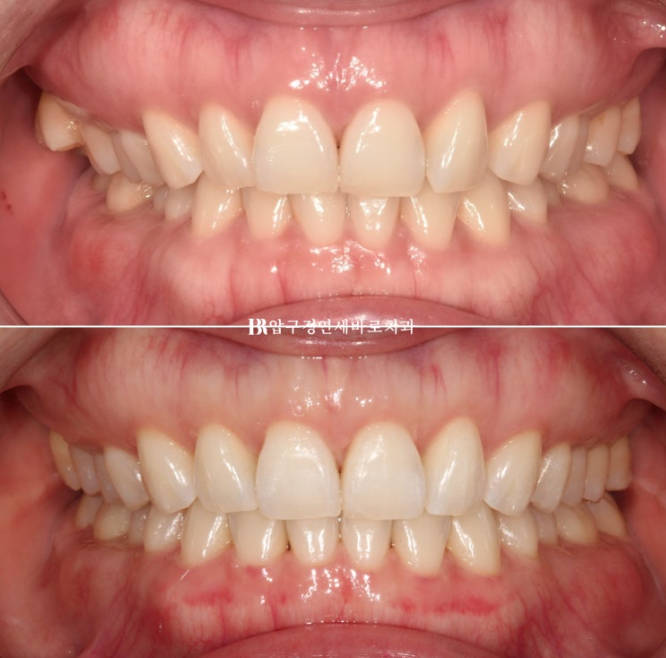

23.07-24.05

미니스크류를 심고 치료하면 인비절라인 라이트로 가능한 케이스였습니다.

23.7

11개월간 치료 후 끝났습니다.

중심선 불일치 그리고 오른쪽의 맨 뒤 큰어금니 바깥으로 나가 있는 가위교합이 정면에서도 잘 보입니다.

24.5

23.07~24.05